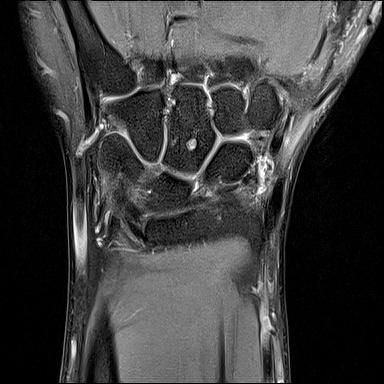

mri는 23년 부분파열 당시

• 1번 째 사진

• 제공해 주신 영상들을 확인했습니다. MRI는 2023년 부분파열 당시 촬영본이고, 단순 방사선 및 CT는 2025년 12월 골절 당시 영상으로 이해하고 검토하겠습니다.

2023년 MRI 영상을 보면, 삼각섬유연골복합체(Triangular Fibrocartilage Complex, TFCC)에 전반적인 신호 변화와 함께 척골 부착부 근처의 손상 소견이 확인됩니다. 당시 봉합술을 시행한 것은 임상적으로 타당한 판단이었습니다. 이후 경과가 양호하다가, 2025년 12월 요골·척골 원위부 골절이 발생한 점이 현재 상황의 핵심입니다.